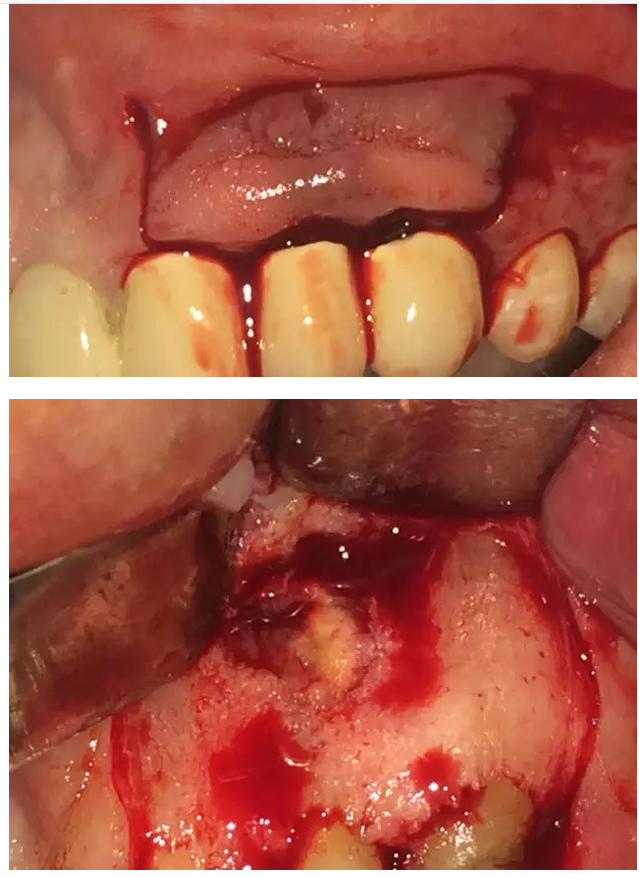

兩例根尖手術(shù)病例欣賞

來源于牙醫(yī)世家